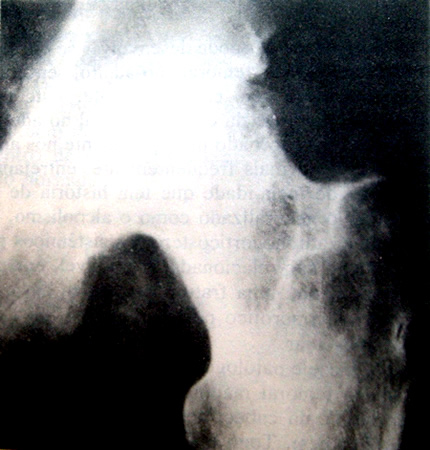

Figura 13-26. Osteocondrite dissecante na superticie convexa da cabeça femoral em um rapaz de 15 anos. O pequeno segmento subcondral de osso necratrico é facilmente observado. Este segmento, entretanto, dificilmente separar-se-á, uma vez que está bem protegido pela superfície articular congruente aposta do acetábulo.